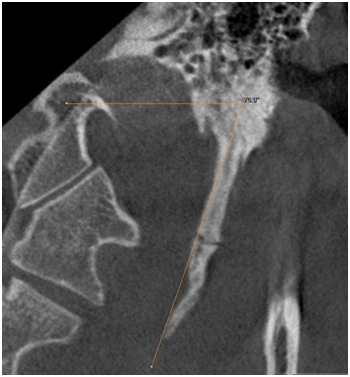

The morphology of SHC was recorded to evaluate the general structural appearance and the number of segments and was categorized into 3 types as single segment ossification, two segment ossification and three segment ossification (Figures 1‒3). The length was defined as the distance between the base of the SP and the tip of the ossified SHC. If there was segmental ossification of the SP, the distance was measured including the non-ossified parts (Figure 4). The antero posterior angle (APA) was defined as the angle made by the process with the perpendicular dropped from the lateral part of the external auditory meatus (Figure 5). The mediolateral angulation (MLA) was defined angle of intersection between the longitudinal axis of the SHC to the perpendicular dropped from the base of the process (Figure 6).

Figure 6 Shows Mediolateral angulation (MLA).